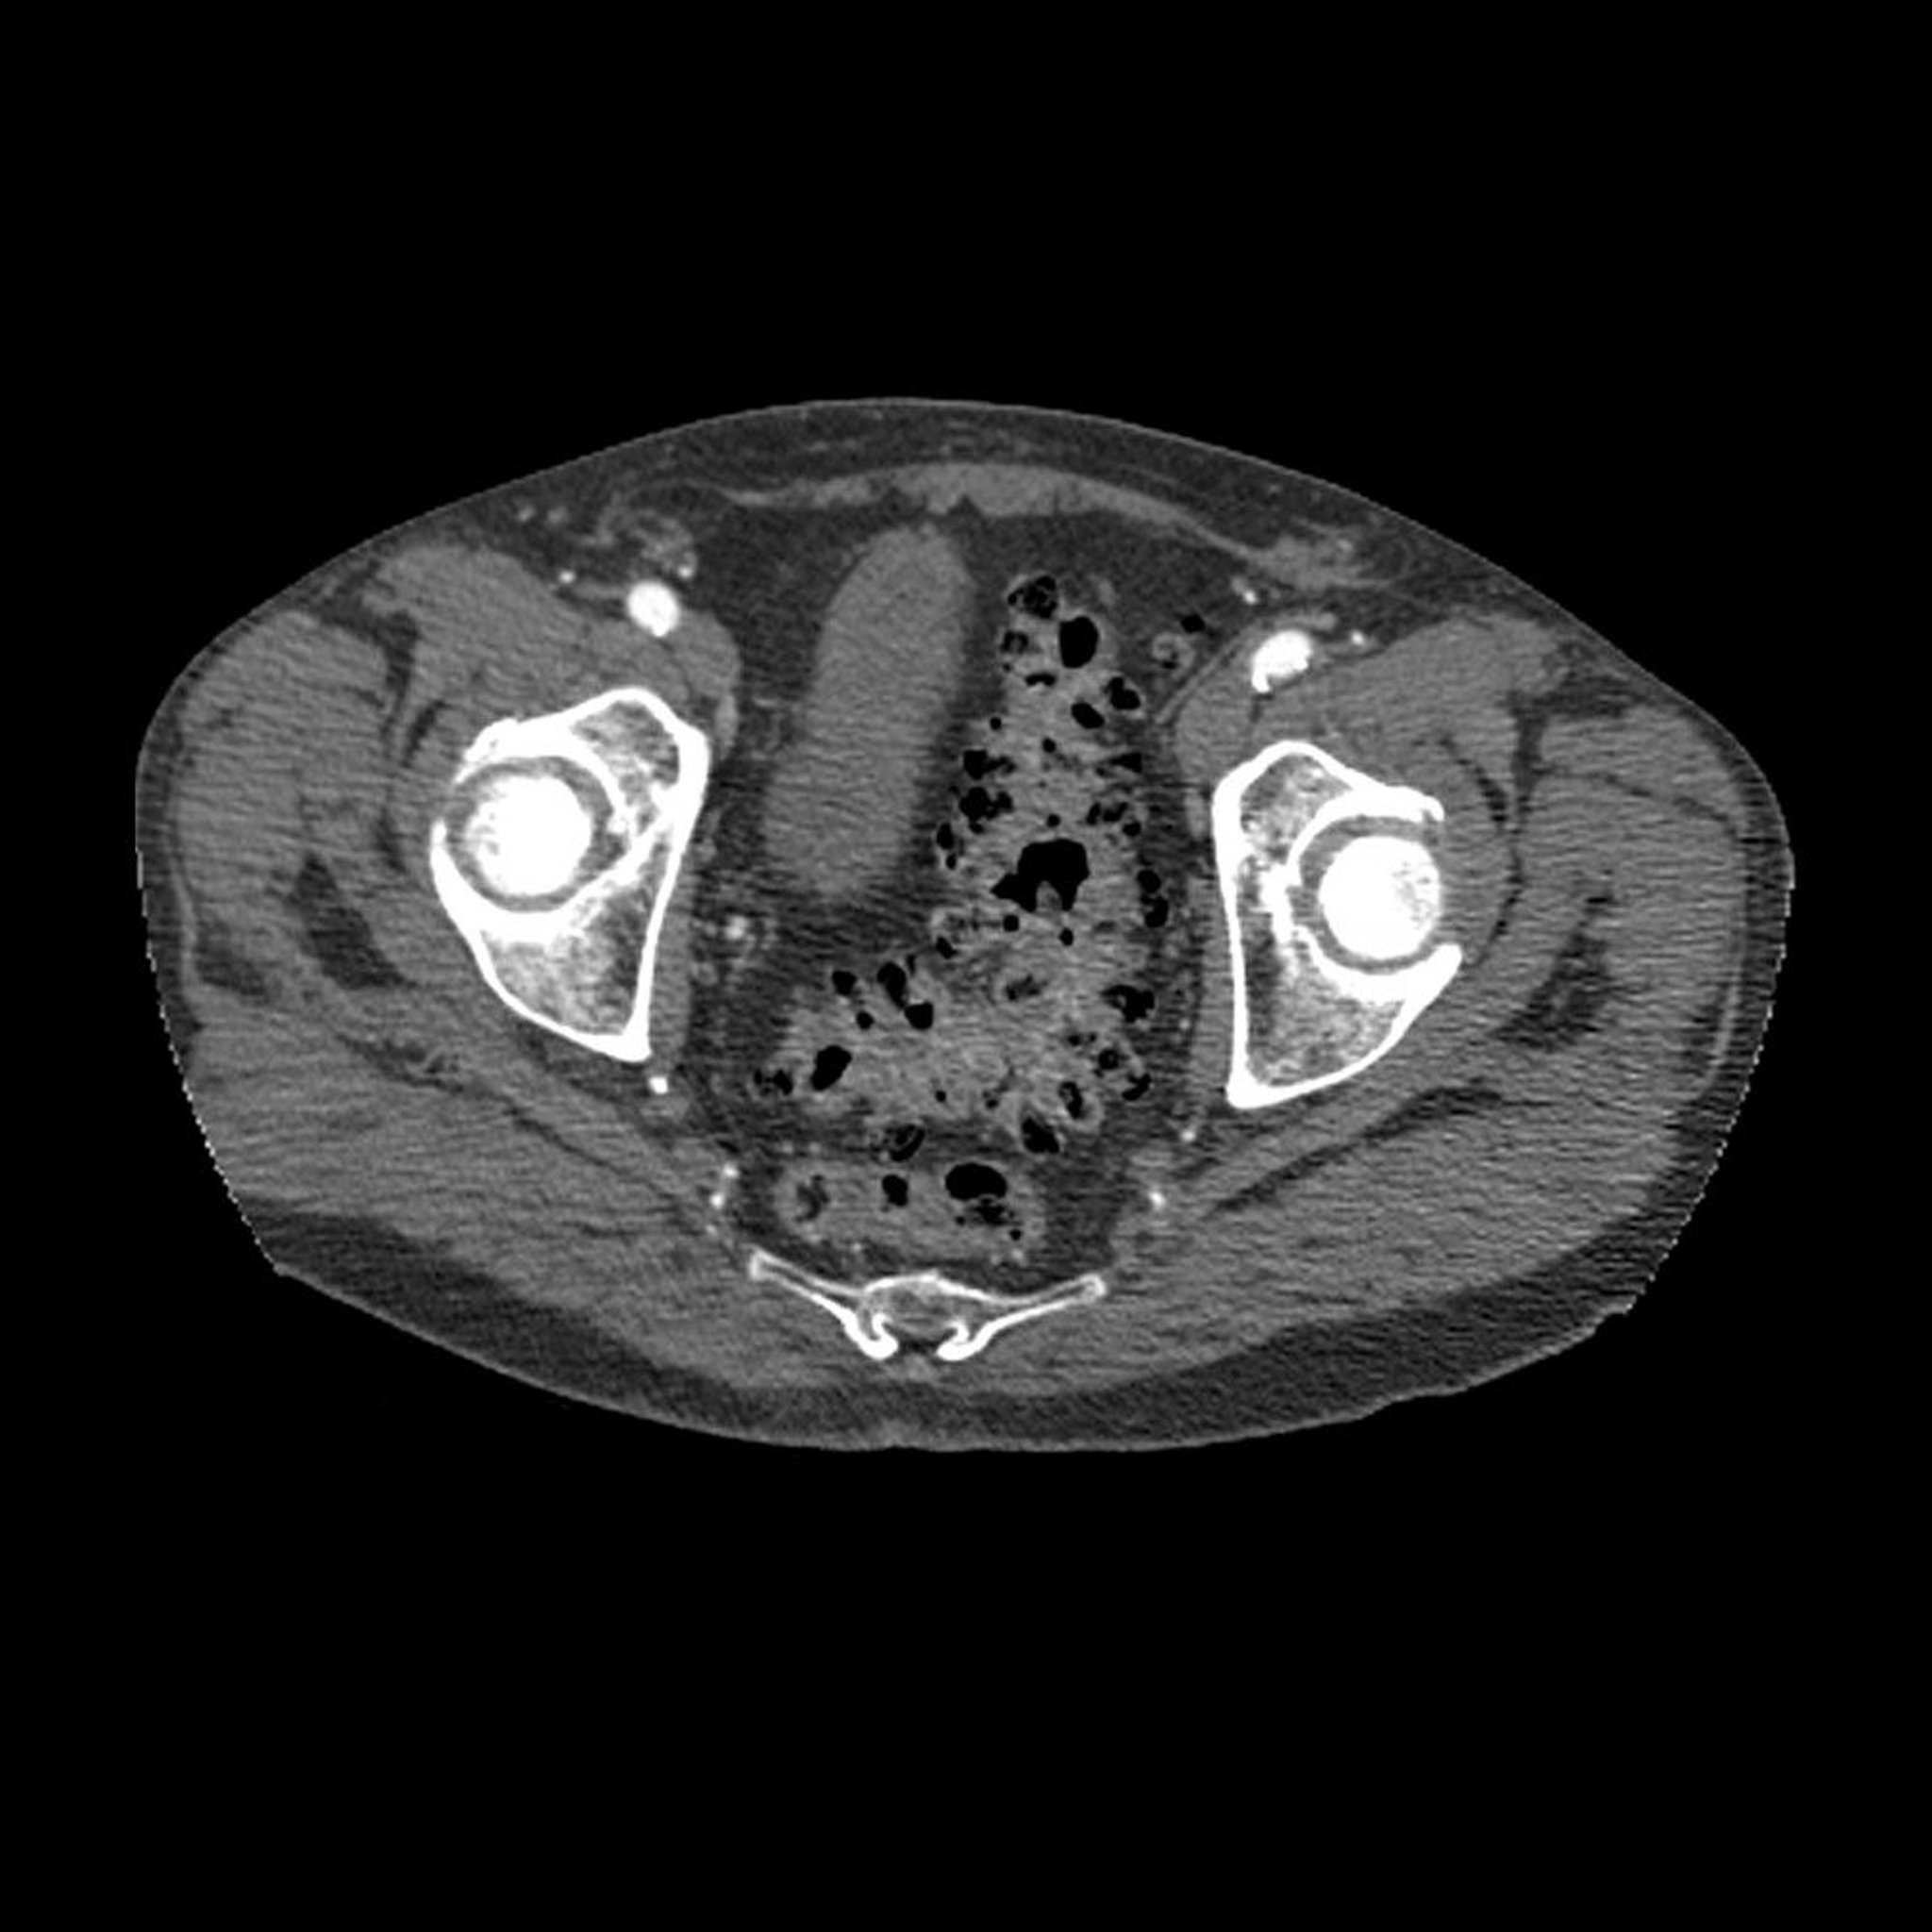

Divertikulose (CT)

Dieses axiale CT-Querschnittsbild durch das Becken zeigt das typische Erscheinungsbild einer Divertikulose (die dunklen Bereiche in der Wand des Sigmas).